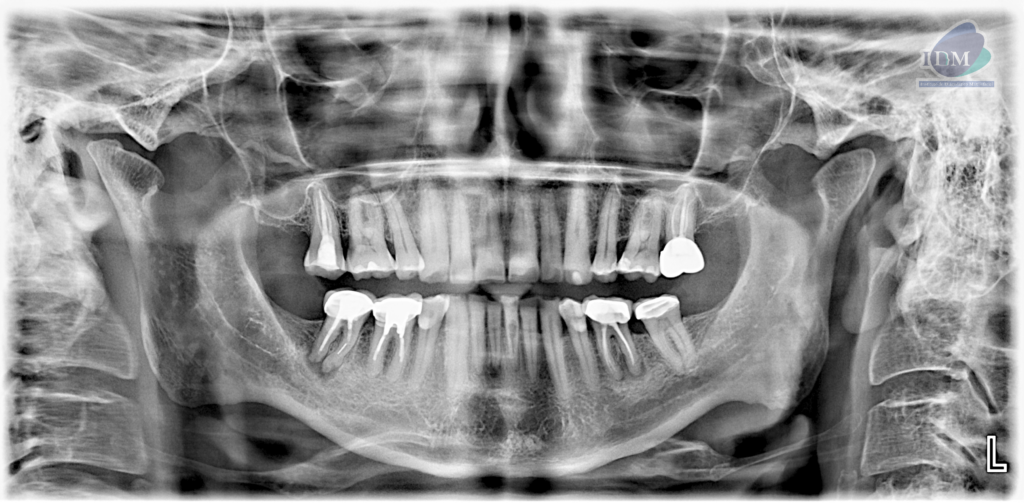

Radiografia Panorámica

A la evaluación de la radiografía panorámica se observan aplanamiento del contorno condilar bilateral, neumatización alveolar de ambos senos maxilares, múltiples coronas protésica, obturación de conductos, así como la presencia de procesos osteolítico periapicales en las piezas 36 y 46; esta última con presencia de una imagen radiopaca en raíz mesial compatible con fragmento de instrumento endodóntico. Finalmente se observa la pieza 41 con un proceso osteolítico periapical y la pieza 31 con una imagen radiolucida proyectada a nivel de tercio cervical.

A la evaluación de la tomografía computarizada cone beam de campo mediano se observa en los cortes axiales, transaxialres y tangenciales la presencia de una imagen hipodensa que se localiza a nivel de tercio cervical de la pieza 31 por debajo del límite amelocementario en la superficie lingual la cual se comunica con el conducto pulpar ocasionando la alteración en su morfología, finalmente se observa un discreto ensanchamiento del espacio para el ligamento periodontal apical, compatible con reabsorción cervical invasiva (RCI)